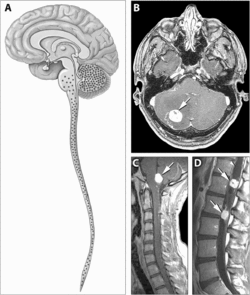

داء فون هيبل لينداو (بالإنجليزية: Von Hippel-Lindau Disease)هو مرض وراثي نادر يسبب نمو أورام وكيسات في جسم الإنسان. وقد تكون هذه الأورام سرطانية أو حميدة، وقد تنمو في الدماغ والحبل الشوكي والكليتين والبنكرياس وفي الجهاز التناسلي عند الرجال. يتميّز هذا الداء بأورام وعائية في شبكية العين والمخيخ وأحياناً في النخاع .[3]

تختلف أعراض داء فون هيبل لينداو وتعتمد على حجم الورم وموضعه، وقد تتضمن الصداع ومشاكل في التوازن والمشي والدوخة وضعف في الأطراف ومشاكل في الرؤية وارتفاع في ضغط الدم.التي لديها قابلية التحول إلى ورم .إن الأشخاص الذين تحوي سلسلتهم الوراثية للجين المتغير في هتش ال، لديهم مخاطر متزايدة للإصابة بسرطان الكلى. قد يعانون كذلك من تكيسات أو أورام في العيون، والدماغ، أو أجزاء أخرى من الجسم..كثيرون من المصابين بسرطان الكلى ليس لديهم أي من عوامل الخطر هذه، والبعض ممن لديهم عوامل الخطر المعروفة هذه لا يصابون بهذا المرض.حيث يكون الأفراد المصابين بالمرض في خطر من تطور ورم أرومي وعائي لكل من المخيخ وجذع الدماغ والنخاع الشوكي كالورم الوعائي الشبكي ,سرطان الخلاية الرائقة,ورم الواتم. سرطان الخلايا الكلوية ، البنكرياس,الخراجات، اللمف الباطن، وcystadenomas حليمي الثنائية من (في الرجال) أو الرباط العريض للرحم (للنساء).[4][5] .ان الورام وعائي يحدث في 37.2٪ من المرضى الذين يعانون من مرض داء فون هيبل وعادة يصيب الشبكية. ونتيجة لذلك، فان فقدان الرؤية هو أمر شائع جدافي هذه الحالة . ومع ذلك، يمكن أيضا الأجهزة الأخرى أن تتأثرب: السكتات الدماغية والنوبات القلبية، وأمراض القلب والأوعية الدموية، وهي أعراض إضافية مشتركة.[6]

ينجم هذا المرض ذو الوراثة السائدة بسبب مورثة معطوبة على الكرومسوم3P25-26 ويتميز بترافق الأورام الوعائية في الشبكية وداخل القحف(في المخيخ بشكل وصفي) مع الأورام الوعائية..[7]